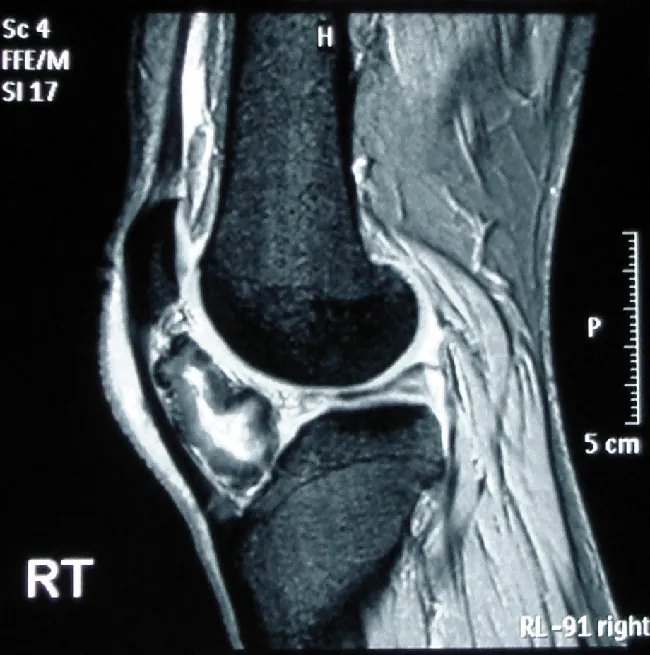

The signals detected by MRI vary with the density of hydrogen atoms and with the nature of their surroundings, allowing identification of different types of tissue and even allowing the visualization of motion. For example, the volume of blood leaving the heart in a single stroke can be measured, and heart motion can be observed. Soft tissues that don’t show up well on X-ray images can be seen clearly, allowing diagnosis of brain tumors, strokes, and other conditions. This technique is also valuable in diagnosing damage to knees or other joints and is a noninvasive alternative to surgical explorations.

An M R I of the knee shows a high-resolution, black and white image of internal structures.

Figure 13.23 If you’re a runner, you really don’t want this to happen to you. The MRI of this left knee shows bone formation in the tissue in a patient with osteochondroma. (credit: “Osteochondroma MRI” by Michael R Carmont, Sian Davies, Daniel Gey van Pittius and Robin Rees/Wikimedia Commons, CC BY 2.0)